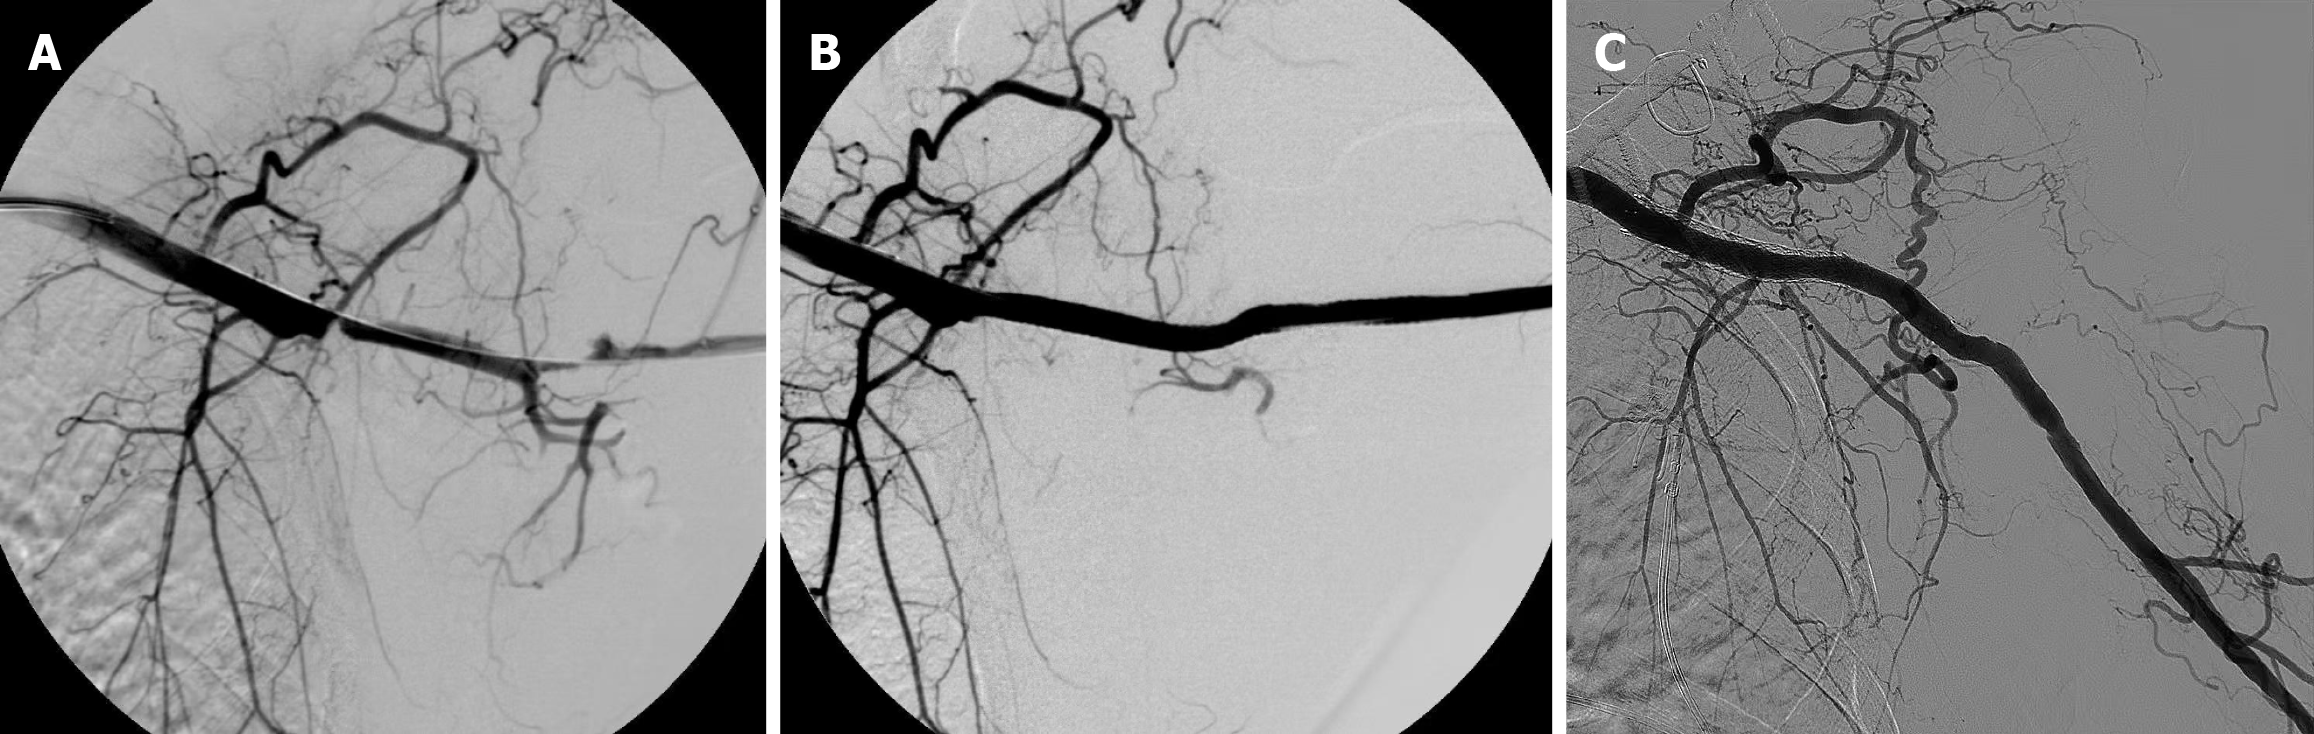

Figure 1 Bare metal stent treatment for brachial artery injury of the upper limb.

A: Angiography showing damage to the brachial artery with local occlusion; B: Immediate post-stent placement angiography; C: Significant improvement in regional blood supply after surgery.